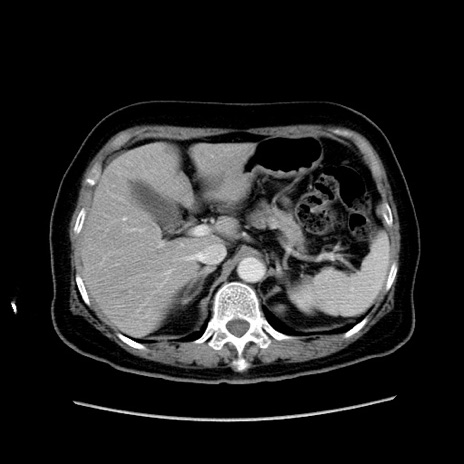

症例19(横断像)

【症例】80歳代女性

【主訴】下腹部痛

【現病歴】約8時間前より下腹部痛の出現あり、救急外来受診。

【既往歴】両側付属器切除

【身体所見】意識清明、下腹部正中に手術痕あり、その部位に一致して圧痛と反跳痛あり。腸蠕動音は亢進。

【データ】WBC 9300、CRP 0.15